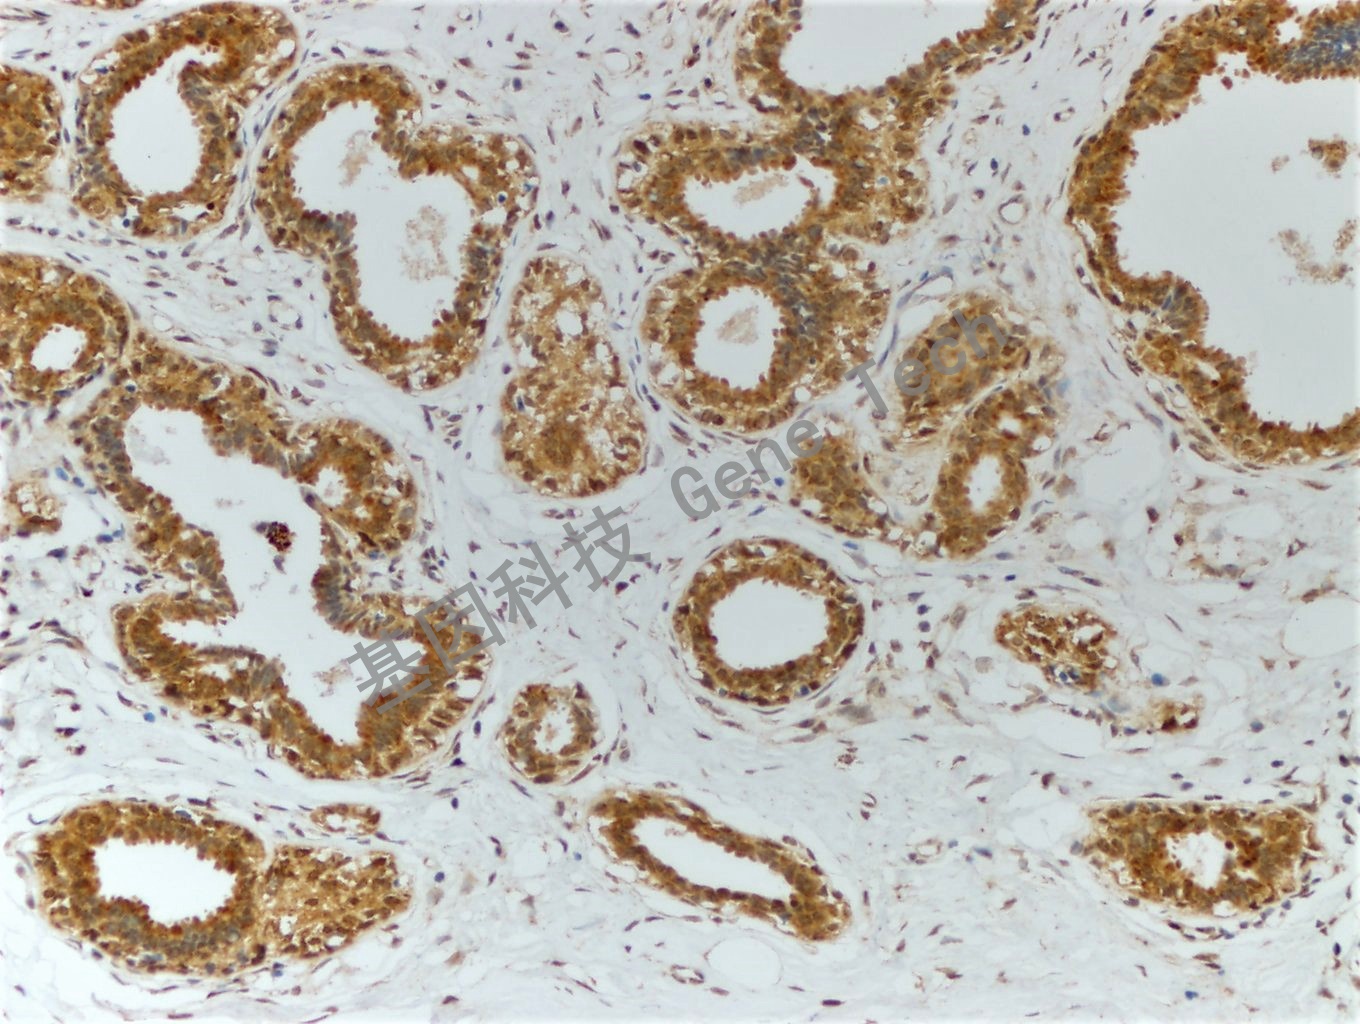

| 乳腺癌石蠟切片,用 PTEN(GT2010)染色,細胞漿/細胞核陽性,DAB 顯色。 | ||

| 預處理:高pH熱修復 | 陽性部位:細胞漿/細胞核 | 陽性對照:乳腺癌 |

| 簡介:PTEN(Phosphatase and tensin homolog, 磷酸酶和張力蛋白同源)也稱 MMAC1或TEP1,是一種腫瘤抑制基因,定位于人染色體10q23。該基因編碼的磷酸酶可調節(jié)細胞周期、凋亡的進程。研究發(fā)現,在人類多種腫瘤和遺傳性腫瘤易感綜合癥疾病中存在PTEN的缺失和突變,在膠質瘤、乳腺癌及前列腺癌中PTEN的表達與病人預后有一定相關性。 | ||